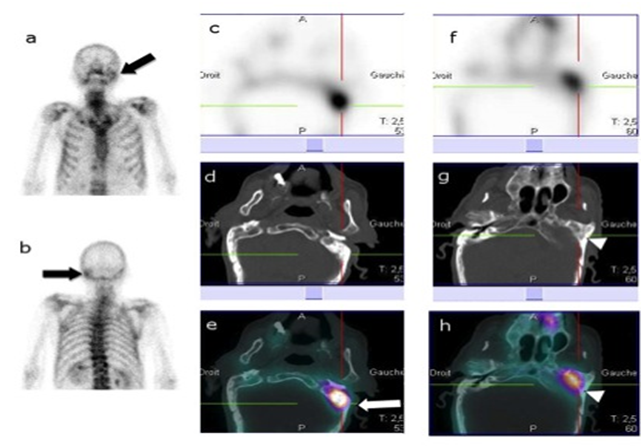

Figure 2, A 63year old diabetic male, presented with unrelenting otalgia and persistent purulent Otorrhea refractory to antibiotics. The clinical exam showed oedema, stenosis and granulation tissue of the external auditory canal. Planar BS (a, b) and SPECT images (c, f) showed increased radiotracer uptake (arrow) in the right temporal bone. CT images (d, g) did not reveal any obvious abnormality. SPECT/CT images (e, h) showed increased radiotracer uptake in the squamous portion (arrow) and tympanic portion (arrowhead) of temporal bone. Considering clinical follow and bone scintigraphy, the final diagnosis was NOE. This case illustrate that bone scintigraphy is more sensitive than CT. SPECT/CT was superior to planar BS and SPECT in accurately locating the involved bone.

Figure 2 The clinical exam showed oedema, stenosis and granulation tissue of the external auditory canal.